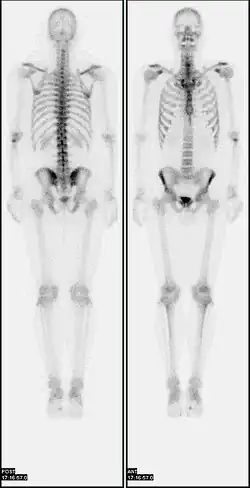

A nuclear medicine whole body bone scan. The nuclear medicine whole body bone scan is generally used in evaluations of various bone-related pathology, such as for bone pain, stress fracture, nonmalignant bone lesions, bone infections, or the spread of cancer to the bone. -